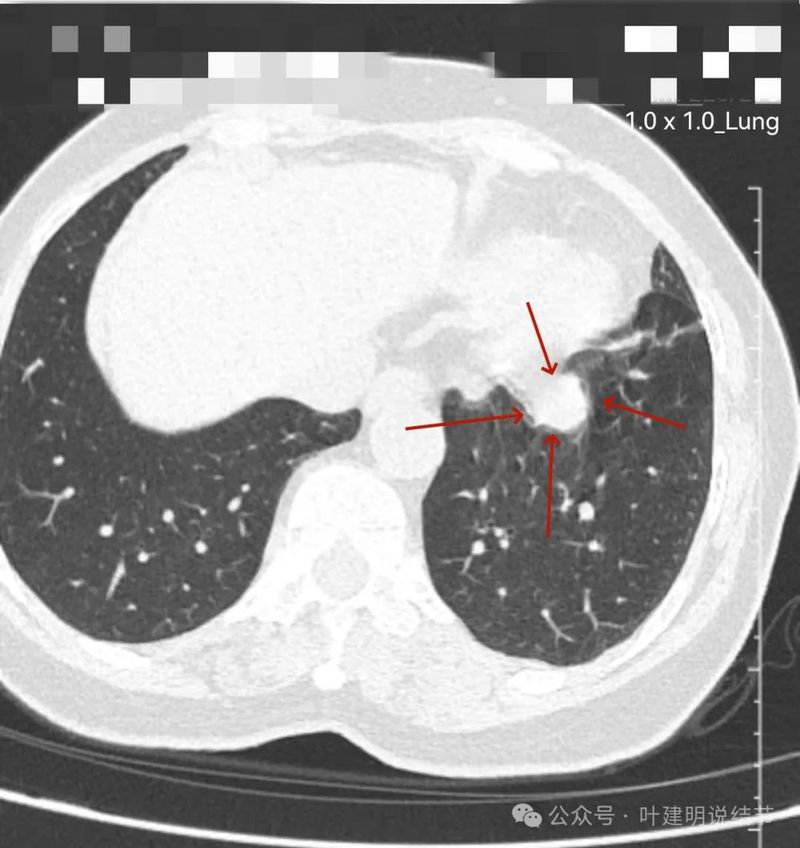

左下实性结节,明显有膨胀感,边缘虽然光滑,但给人感觉不舒服,恶性的可能性大些。

再看左下主病灶连续层面与重建影像:

冠状位见病灶与周围结构有间隙,说明不像炎性,如果是炎症,挨这么近,一般会搭牢的。

矢状位病灶膨胀感不如横断们与冠状位明显,但东西是实性的。

轴位病灶实性,分叶,膨胀!

病灶表面不平,有浅分叶,与膈肌之间有间隙。

与膈肌之间间隙明显,病灶实性,膨胀性明显,边缘相对较为光滑。

病灶浅分叶,膨胀性,周围有很淡的磨玻璃密度似的,这可能是检查时屏气屏得不太好的关系,不太符合混合磨玻璃结节的样子。

整体感觉较圆,膨胀性是明显的。膈肌有点被它顶过去的样子。

上图层面相对最大,感觉鼓鼓的。

边界与轮廓清。

上图显得膨胀感欠了点,但分叶与表面不平是明显的。

边比较为平直,密度仍实。

感觉两处不同的中心,如果连续层面看,应该是病灶不平的关系,与膈肌间仍有间隙,密度是实性的。

边缘区域的样子。

纵隔窗见病灶实性密度,与膈肌间有低密度线状间隙。

病灶密度稍不均。

较为边缘部分的纵隔窗样子。